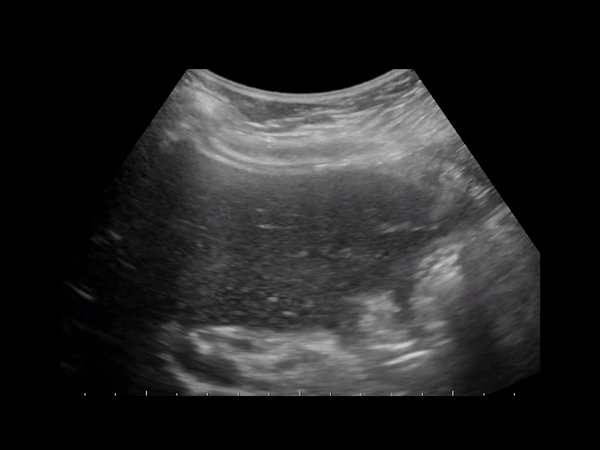

On ultrasound you’ll see low level echoes to echogenic debris that layers in the dependant part of the GB and is mobile with patient position. Sludge may aggregate into clumps which may simulate masses or polyps. This is known as tumefactive sludge. The gallbladder may also be completely filled with sludge making the whole GB complex isoechoic to the liver known as hepatization.

GB stasis and ischemia or biliary blockage by sludge. The GB is typically distended with wall thickening >0.3cm, pericholecystic fluid and/or wall edema in the absence of ascites or hyperalbuminemia. AC usually presents in critically ill patients with sepsis and with jaundice without a clear cause. Complications are similar to calculous cholecystitis including emphysematous cholecystitis, gangrene and perforation.